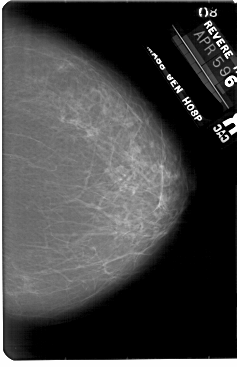

A_1855_1.RIGHT_MLO

RIGHT_MLO LINES 5491 PIXELS_PER_LINE 3796 BITS_PER_PIXEL 12 RESOLUTION 43.5 NON_OVERLAY